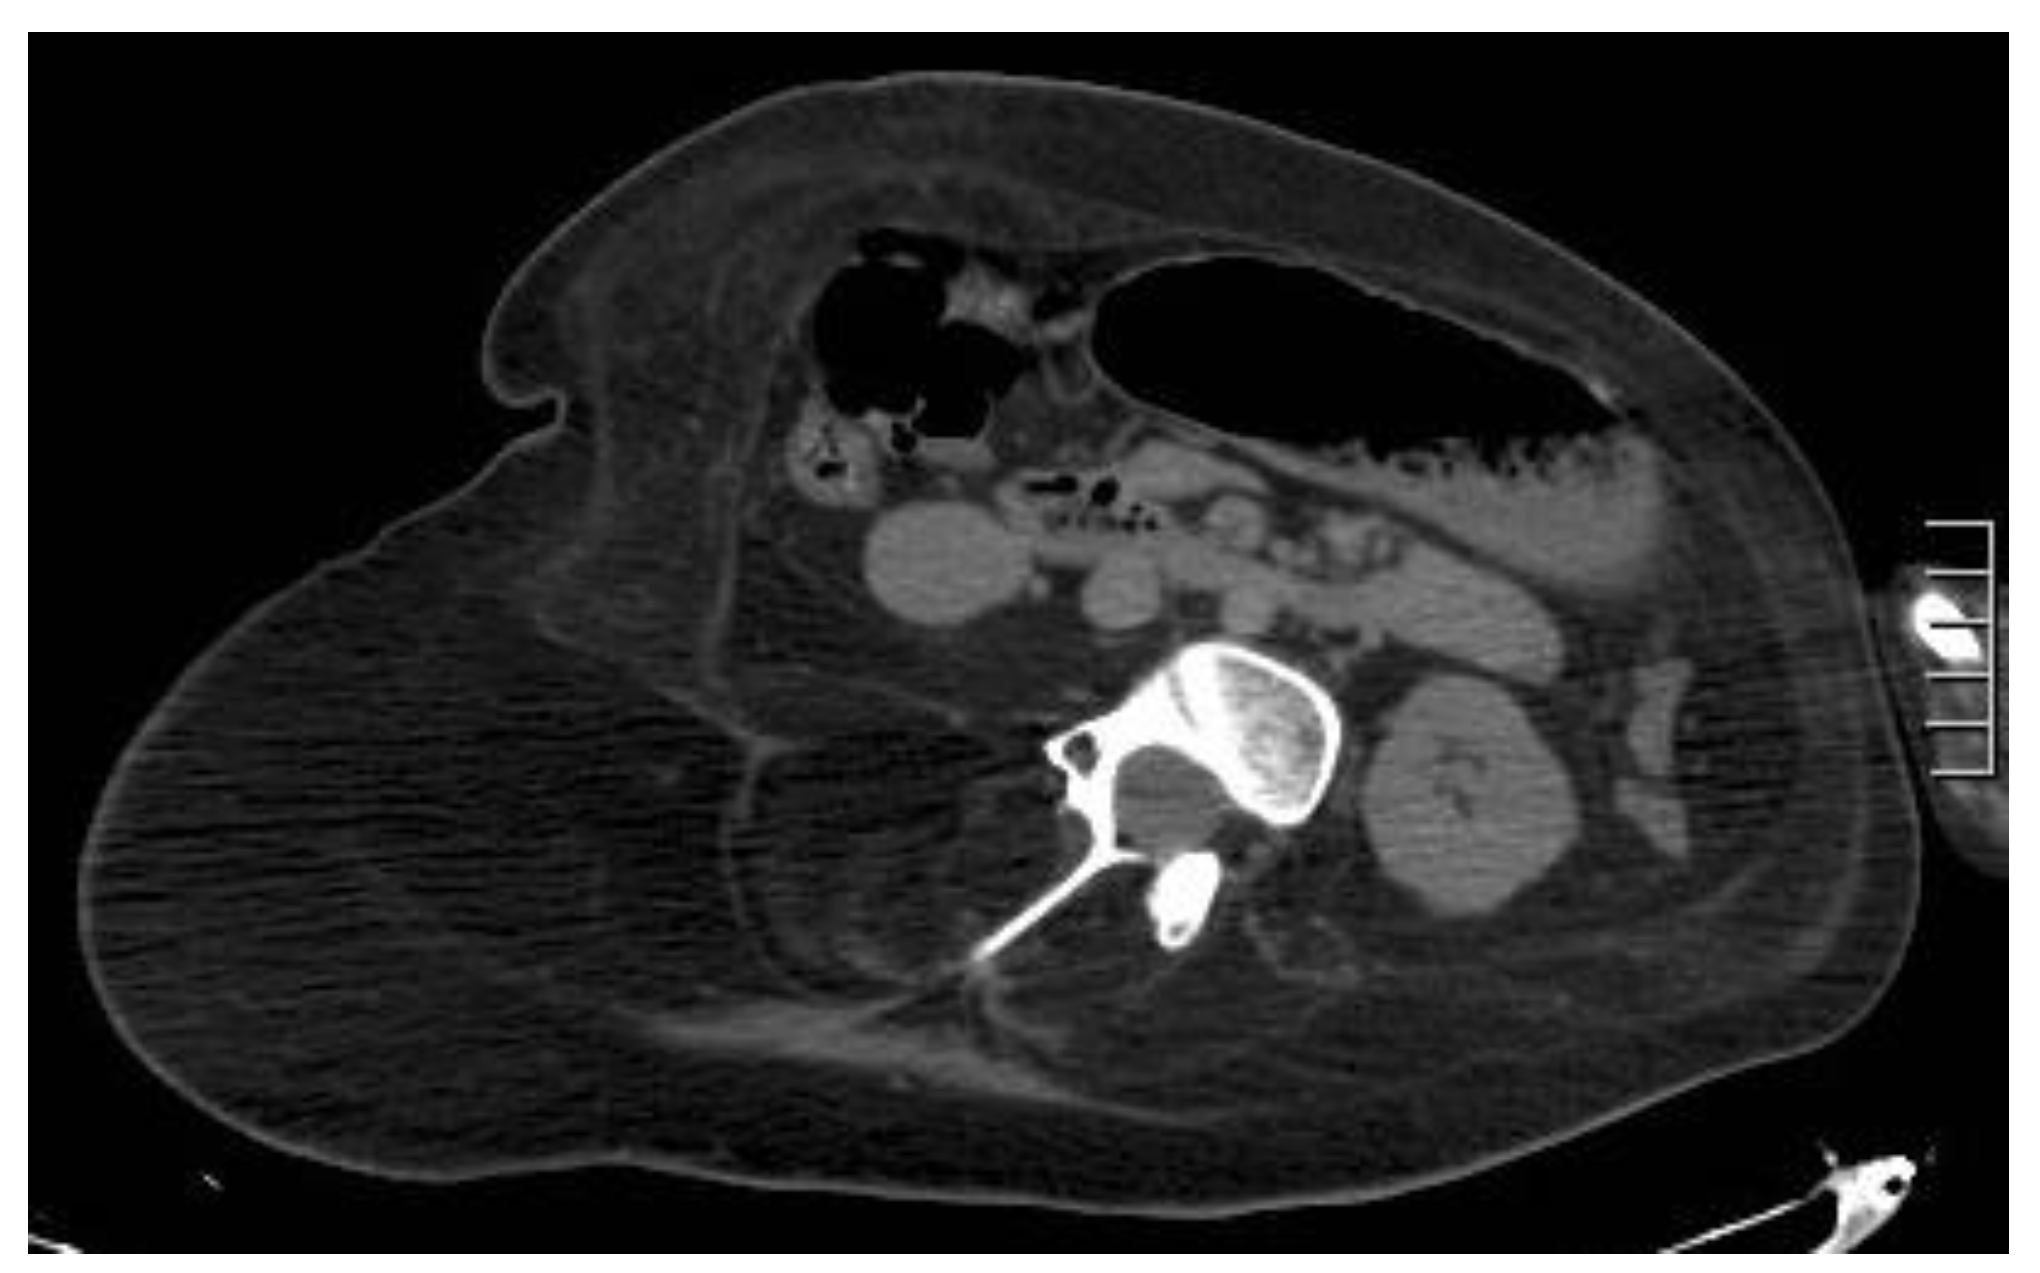

5.5. Splenosis